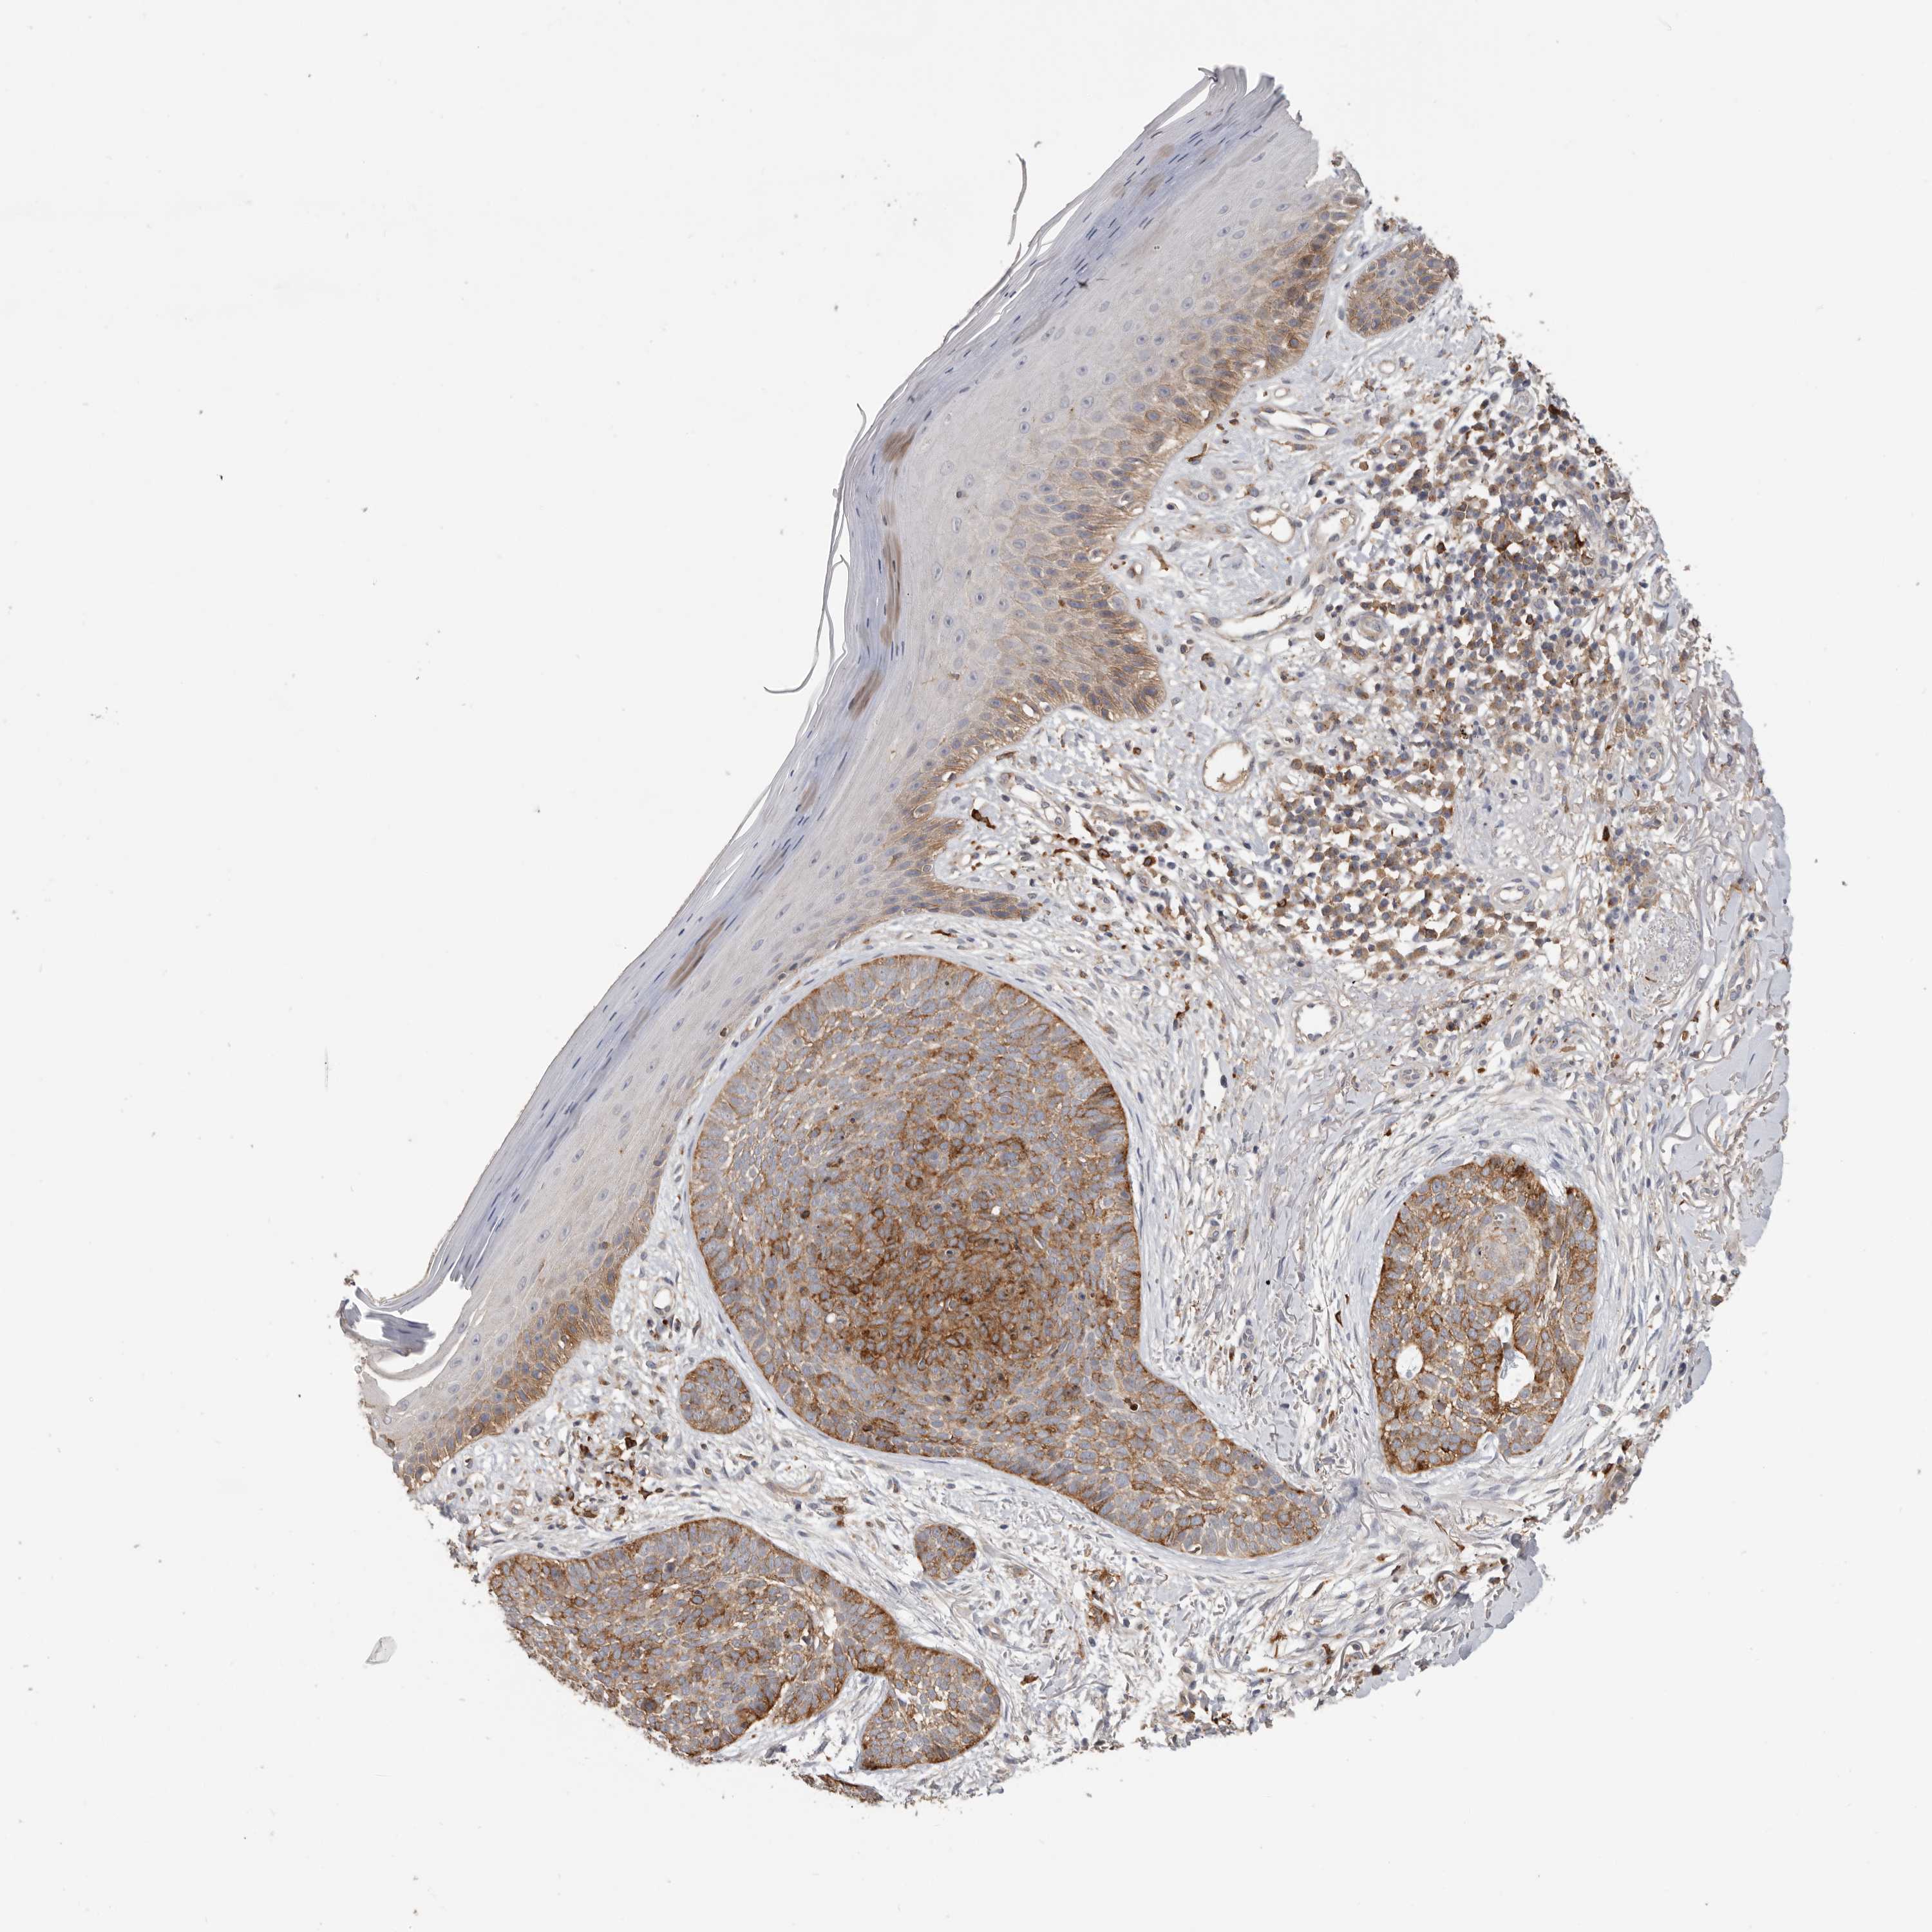

Basal cell and squamous cell cancer

SKIN CANCER - Protein expressioni

A mouse-over function shows sample information and annotation data. Click on an image to view it in a full screen mode. Samples can be filtered based on level of antibody staining by selecting one or several of the following categories: high, medium, low and not detected. The assay and annotation is described here.

Antibody staining in the annotated cell types in the current human tissue is reported as not detected, low, medium, or high, based on conventional immunohistochemistry profiling in selected tissues. This score is based on the combination of the staining intensity and fraction of stained cells.

Each image is clickable and will lead to virtual microscopy that enables deeper exploration of all samples and also displays staining intensity scores, fraction scores and subcellular localization as well as patient and tissue information for each sample.

Antibody HPA028598

Antibody CAB000153

Basal cell carcinoma

Squamous cell carcinoma, NOS

Squamous cell carcinoma, metastatic, NOS